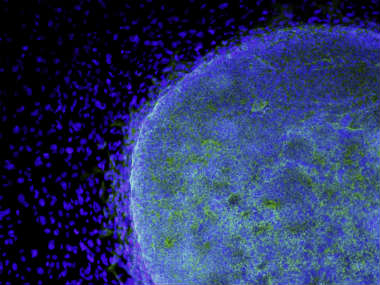

Tokyo: In a major boost to stem cell research, a Japanese patient with a debilitating eye disease is set to become the first person in the world to be treated with induced pluripotent stem cells. A 19-member health ministry committee here vetted the researchers’ safety tests and cleared the team to begin the experimental procedure, the scientific journal Nature reported. Masayo Takahashi, an ophthalmologist at the RIKEN Center for Developmental Biology (CDB) in Kobe has been using induced pluripotent stem (iPS) cells to prepare a treatment for age related macular degeneration. The Japanese team will now use iPS cells to treat the patient with degenerative eye disease. During her research on mice and monkeys, Takahashi took skin cells from people with the disease and converted them to iPS cells. [caption id=“attachment_1708853” align=“alignleft” width=“380”] A microscopic view shows a colony of human embryonic stem cells (light blue) growing. Representational image. Reuters[/caption] She then coaxed these cells to become retinal pigment epithelium cells and then to grow into thin sheets that can be transplanted onto the damaged retina. In monkey studies, iPS cells generated from the recipients’ own cells did not provoke an immune reaction that caused them to be rejected. They are capable of becoming any cell type in the body and have the potential to treat a wide range of diseases. The news could be a welcome boost for the CDB which has been mired in controversy over studies on stem cell research that were later retracted, the Nature report added. IANS